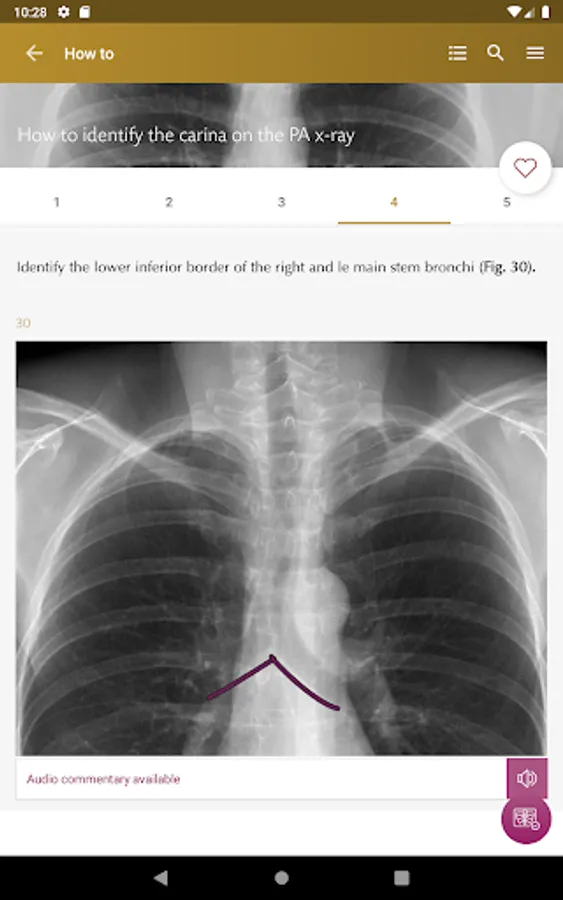

How To’s – 34 step-by-step guides, with annotated x-rays, to illustrate key skills needed to confidentially interpret chest x-ray.